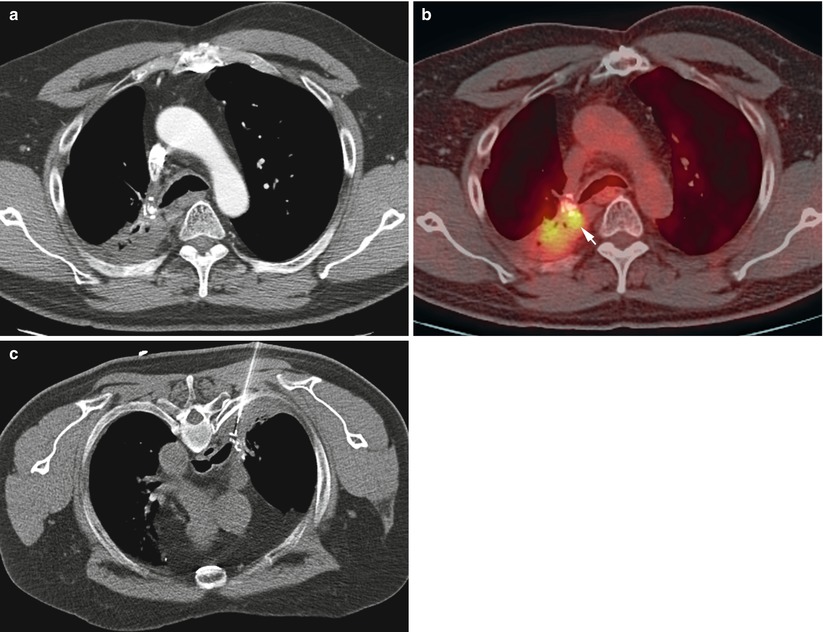

from radiologykey.com

CTGuided Biopsy Radiology Key